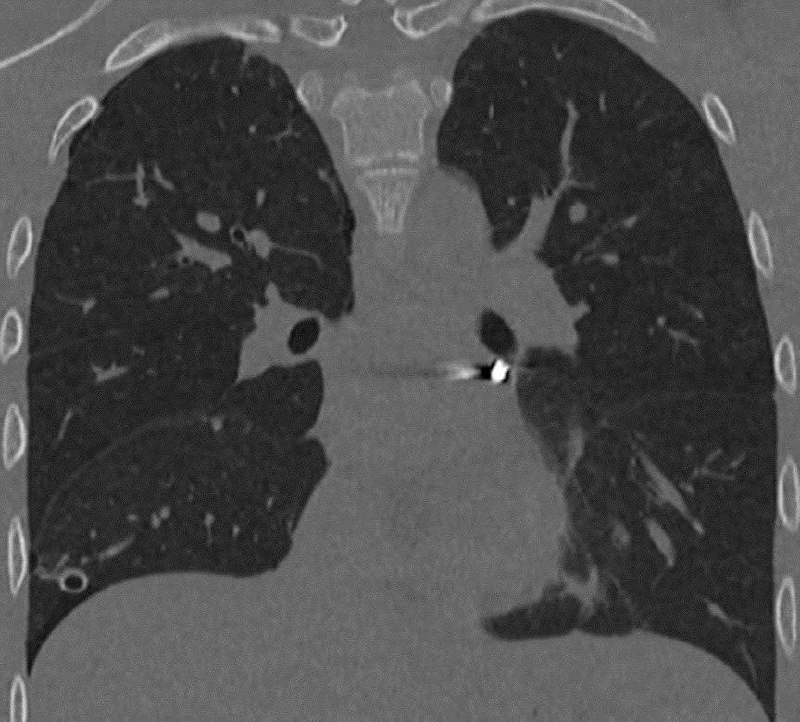

Врачи спасли подростка с пулей в сердце. В 16-летнего парня случайно выстрелил друг из пневматического пистолета. Подростка доставили в Детский центр им. Рошаля в Подмосковье. Там выяснилось, что пуля застряла в перикарде — оболочке сердца. Хирурги работали буквально в миллиметрах от жизненно важных структур сердца, в условиях движения мышц и ограниченного обзора. Операция прошла успешно, пулю достали. Сейчас молодой человек уже дома. ⭕️ Подписаться | Мы в MAX | Буст

Врачи спасли подростка с пулей в сердце. В 16-летнего парня случайно выстрелил друг из пневматического пистолета.

Подростка доставили в Детский центр им. Рошаля в Подмосковье. Там выяснилось, что пуля застряла в перикарде — оболочке сердца. Хирурги работали буквально в миллиметрах от жизненно важных структур сердца, в условиях движения мышц и ограниченного обзора.

Операция прошла успешно, пулю достали. Сейчас молодой человек уже дома.